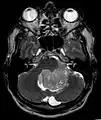

Les épendymomes supratentoriels (SE) représentent entre 40% et 60% des tumeurs intracrâniennes. Localisées au niveau supratentoriel, ces tumeurs apparaissent comme des grosseurs peu homogènes, présentant des zones kystiques, des calcifications mais également des zones hémorragiques et nécrosées.

Aspect radiologique à l’IRM en séquence T1 après injection de Gadolinium d’un épendymome supratentoriel, caractérisé par une lésion bien délimitée du lobe frontal gauche avec prise de contraste hétérogène et des zones de nécrose.